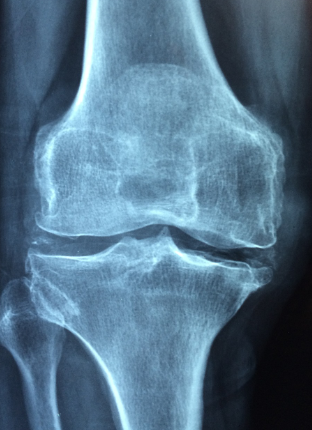

골다공증은 뼈가 약해지고 부러질 위험이 커지는 질환입니다. 나이가 들수록 발생 가능성이 높아지며, 특히 여성에게 더 많이 나타납니다. 골다공증을 예방하고 관리하기 위해서는 올바른 음식 섭취와 건강한 생활습관이 중요합니다.